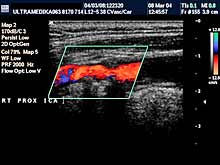

A) Krvni sudovi vrata

Vrsta i sadržaj pregleda:

- Pregled velikih krvnih sudova vrata CD i CPA

modom (obavezno karotidnih i vertebralnih arterija celim tokom).

Pregled podrazumeva procenu ukupne debljine krvnih sudova (indirektna

procena koronarne bolesti), procenu stepena suženja, karakteristika aterosklerotičnog plaka, procena hemodinamike i postavljanje

indikacija za operativno lečenje.

Primenjena tehnika:

- Sono CT,

- XRes,

- 2D Broad band,

- Broad band - CD,

- CPA ,

- CPD.